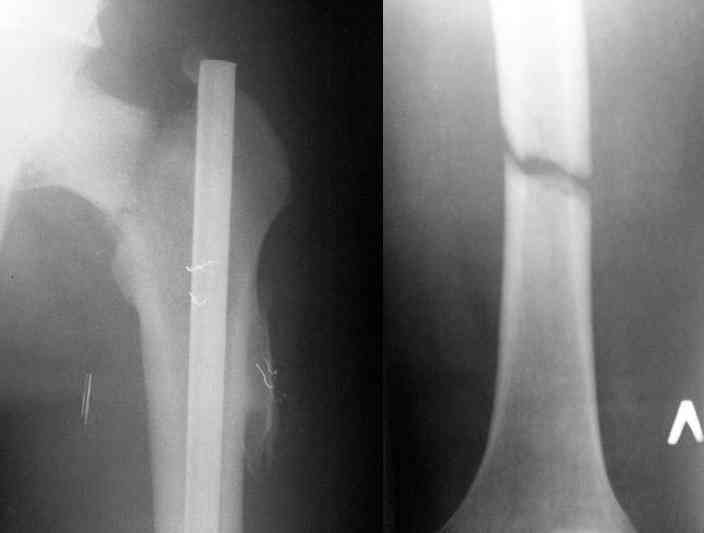

Здесь представлены снимки больного 65 лет, поступившего с диагнозом перелом

бедра после автоаварии.

В первый же день произведено антеградное штифтованием DePuy Trochanteric Nail.

На второй день (7) обнаружен пропущенный перелом,

сделаны Компьютерная Томограмма

и проведены шурурпы через и спереди штифта без удаления.

Послеоперационные снимки